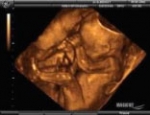

En caso de que no están familiarizados con el término, la endometriosis es una condición donde el recubrimiento endometrial del útero, crece fuera del útero y crece a menudo en los ovarios y los tejidos circundantes. (incluso incluyendo la vegiga y los intentinos).